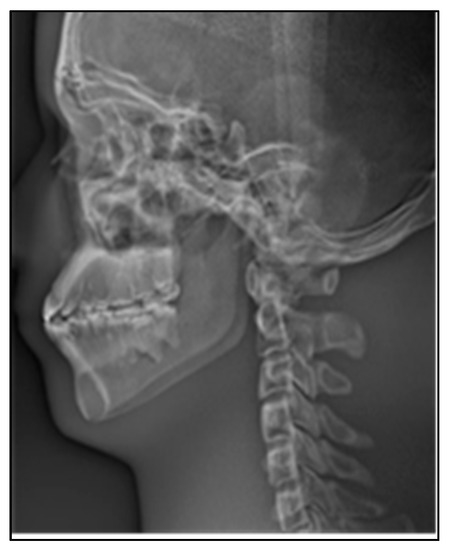

In order to verify the excellent ability of the algorithm in this paper to stitching images of lateral cranial sequences, we compared it with three different stitching methods. The stitching results of the algorithm in this paper are shown in Figure 16a; panoramic images have no stitching gaps and ghosts and the information remains intact during the stitching process. Ref. [38] uses SIFT to extract features for stitching, resulting in information loss in boneless areas of lateral cranial images, as shown in Figure 16b. Ref. [39] uses the combination of normalized cross-correlation and threshold method to stitching the image, but there was much false stitching and ghosting in the complex texture area, as shown in Figure 16c. Ref. [14] uses the strategy of SIFT combined with mutual information (SIFT-MI) to make up for the shortcoming of failing to extract feature points, however there are obvious ghosts and stitching gaps in some areas, as shown in Figure 16d. Ref. [40] uses an improved phase correlation (PC) algorithm and weighted blending to generate panoramic images, and there are a lot of information missing and stitching errors in the image, as shown in Figure 16e. Ref. [41] uses a new and improved algorithm based on the Accelerated KAZE (A-KAZE) Features, and there are significant stitching errors in the cervical stitching of the image, as shown in Figure 16f.

Figure 16.

Sequence image stitching results by different algorithms. (a) This article, (b) SIFT-PSO, (c) NCC, (d) SIFT-NMI, (e) PC, (f) A-KAZE.

Through the above discussion, it is obvious that the stitching algorithm proposed in this paper can complete the continuous stitching of dental lateral cephalic sequence images. The image quality evaluation results obtained are shown in Table 1. Compared with the other Five algorithms, although the running time of the algorithm in this paper is slightly longer than that of some algorithms, the image quality after stitching is better. The maximum information entropy of the method in this paper indicates that the retained information is the most complete. The maximum standard deviation and evaluation gray value indicate that the brightness transformation of the image obtained by the algorithm in this paper is uniform and the image details remain intact. The success rate of the proposed algorithm in this article is higher than that of other algorithms, which indicates that the proposed algorithm has good stability.

Table 1.

Different stitching algorithms quality evaluation parameters.